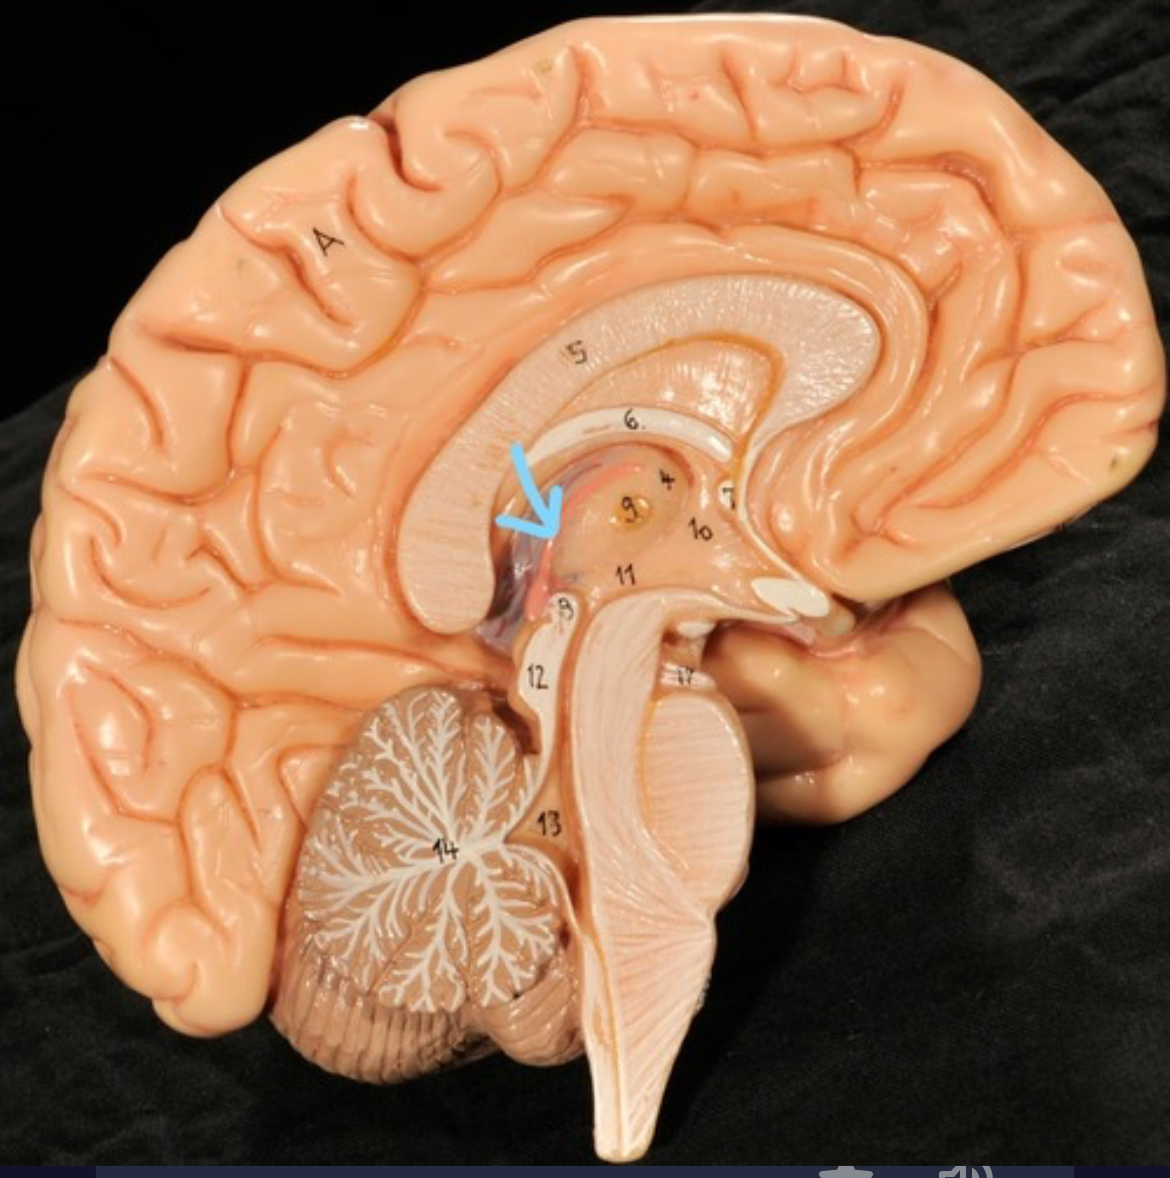

Corpus callosum

Diencephalon

Thalamus

3rd ventricle

Hypothalamus

Epithalamus (pink line)

Brain stem

Pons

Medulla oblongata

Choroid plexus of 3rd ventricle

Cerebral aqueduct (midrain)

4th ventricle

central canal